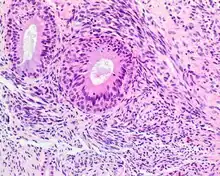

- Infiltrative, highly cellular spindled cell neoplasm is poorly circumscribed and unencapsulated. Bone destruction or invasion is common. The cells show medium to long fascicles (nerve fibers), with a herringbone pattern. The cells are remarkably uniform with elongated nuclei. Delicate strands of intercellular collagen without ropy or dense deposition are seen. A very characteristic concurrent surface-type respiratory epithelial proliferation is found from the surface or in small cystic spaces around the cancer cells, often forming glands. The background may have a rich vascularity and usually has a small number of scattered lymphocytes. Extra growths or mitoses are rare, while necrosis, ulceration, and hemorrhage are usually absent.

- S100 protein (a tumor marker protein) is focal, patchy to diffuse in all tumors.

S100 protein reaction in a biphenotypic sinonasal sarcoma - Smooth-muscle actin or muscle-specific actin is seen in nearly all tumors, but a strong and diffuse reaction with SMA is seen in only about 50% of cases.